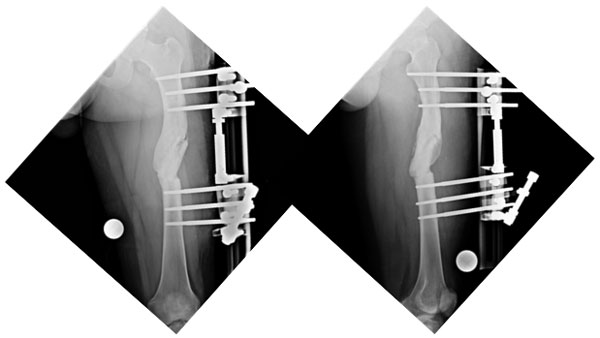

| The x-rays at presentation showing the angulations of the femur at the fracture site. The picture on the left is as seen from the front with red lines showing the axes of the upper and lower segments. The angle between the two axes was about 34°, which should be 0° normally. The picture on the right is from the side and shows the angle between the axes (red Lines) to be about 20°, which is about 12-14° normally. |

| The x-ray after surgery showing correction of axis. |